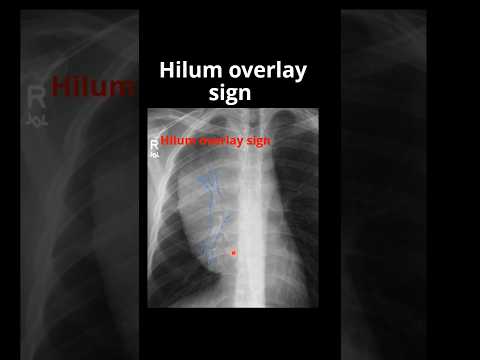

Hellow guys, Welcome to my website, and you are watching Anatomy Thorax 265 Content of Root of Lung Hilum viva. and this vIdeo is uploaded by MBBS VPASS at 2024-01-23T06:45:33-08:00. We are pramote this video only for entertainment and educational perpose only. So, I hop you like our website.